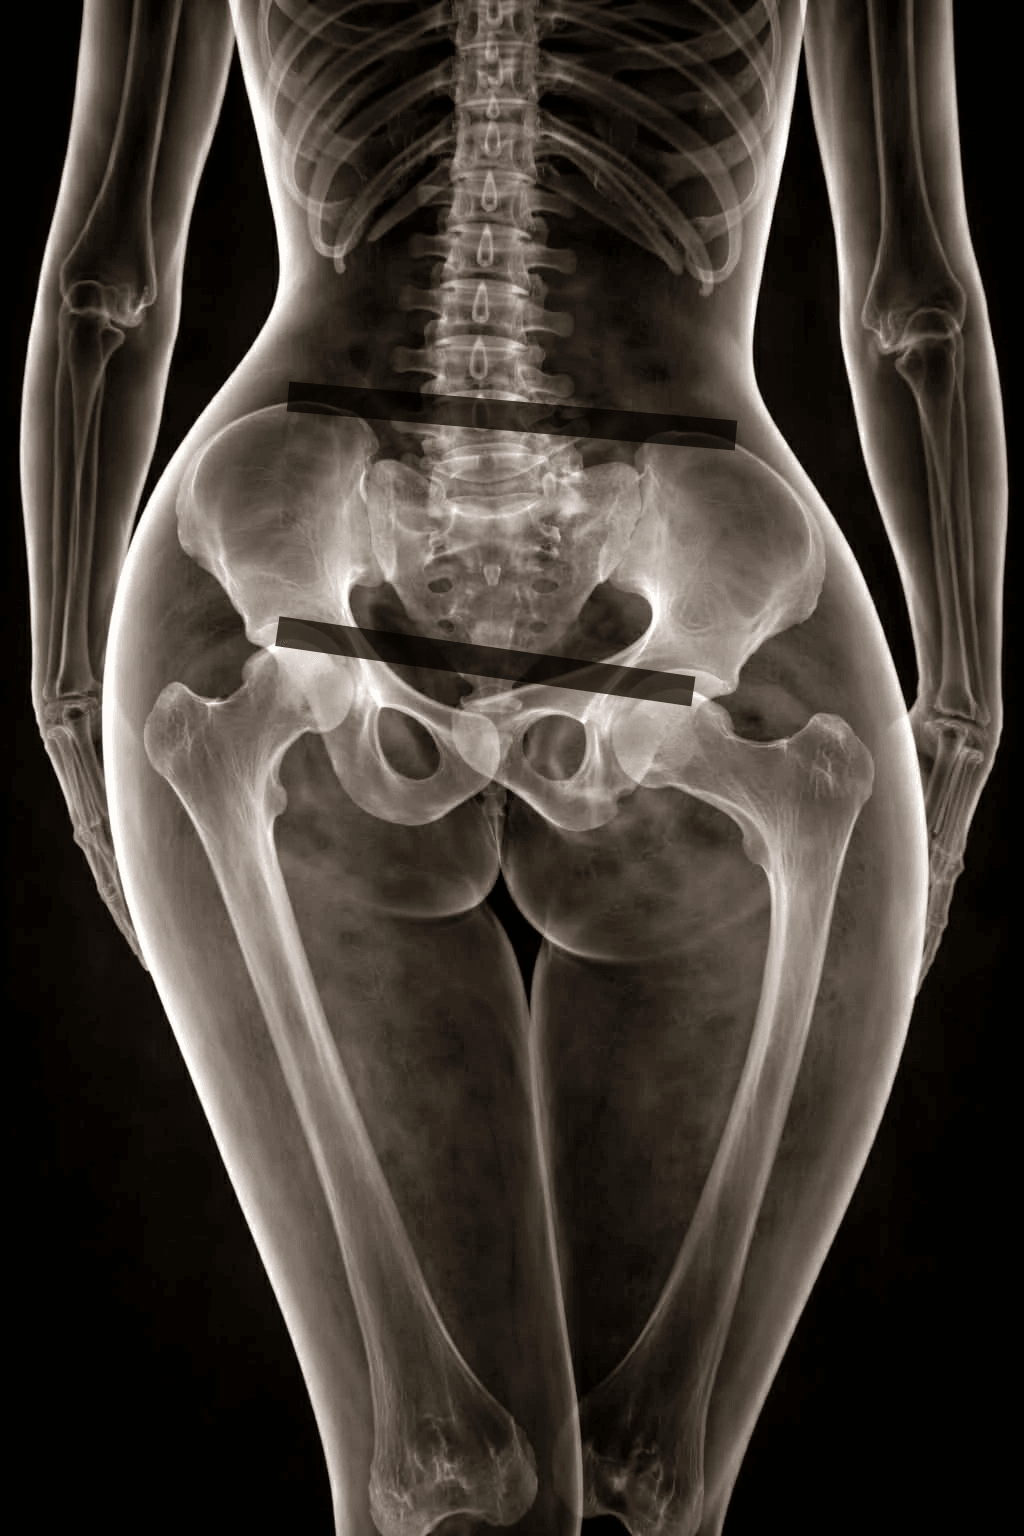

Shoulder asymmetry is not yet a true postural defect—it is rather a deviation / faulty posture. Lowering of one shoulder compared to the other may be linked to careless posture, incorrect habits, or spending too much time in a sitting position. The first symptom that should concern us is back pain and tension. Over time, joint cartilage degeneration may occur. A common cause is pelvic rotation.

The pelvis plays a key role in spinal alignment. Due to a long-lasting incorrect pelvic position, permanent changes may develop in the lumbar, thoracic, and cervical spine. As a result, irreversible damage to intervertebral discs, facet joints, or hip and knee joints may appear, causing pain.

The pelvis is also closely related to body symmetry. It carries the entire vertebral column and has a direct connection with the lower spine and lower limbs. Because of that, any movement of the pelvis results in changes in vertebral position and affects lower-limb movement.

Scientists analyzing biomechanical disorders have noticed that incorrect alignment between spinal sections may lead to pathological conditions. The pelvis is the foundation of the spine, and its correct positioning strongly affects the maintenance of normal spinal curves. What happens in the pelvic girdle can also influence the cervical spine. Therefore, it is important to assess every spinal section, even if the patient complains.

In one study, the cause of vertebral fixation in over 80% of 105 patients was uneven weight bearing between the lower limbs exceeding 5 kg. After manipulation of fixed vertebrae, more than 70% of them were able to distribute weight equally while standing on two scales. Recurrence of the results after this treatment was found in 85% of patients. Better outcomes were observed when the fixed vertebrae were located in the upper cervical spine. If, during the two-scale standing test, a large difference in weight distribution between legs is detected, the craniocervical junction should be examined, including C2–C3. A difference of less than 2 kg does not seem significant.